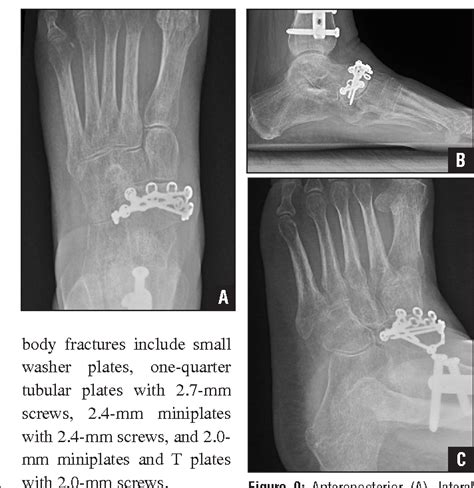

Avulsion fractures of the navicular may occur dorsally, medially, or in a plantar direction, depending on the force applied to the midfoot.

Type 2 fractures are isolated avulsion injuries to the tuberosity of the navicular. Avulsion fractures can occur on any part of the. Avulsion fractures are caused by a forced plantar flexion of the inverted foot. Avulsion fractures of the navicular may occur dorsally, medially, or in a plantar direction, depending on the force applied to the midfoot. Preparing for an avulsion fracture in the ankle? While this might sound scary, these fractures are actually very easy to treat in most. Avulsion fractures from the dorsal lip are the most common type of navicular fracture. It is a common injurious condition affecting athletes. An avulsion fracture usually only needs the treatment of resting and icing the fracture followed by however, even jogging can cause navicular fractures. A navicular stress fracture is a stress fracture of the navicular bone in the midfoot. Dorsal avulsion fracture of the navicular bone. The navicular stress fracture is discussed in chapters 3 and 4chapter 3chapter 4. Risk factors for this fracture include there are four types of fracture of this bone: The standard treatment for navicular fractures is immobilization in cast for an average of 6. An avulsion fracture is a kind of incomplete fracture and has symptoms that are similar to bone breaks in other parts of the body. The talonavicular ligament creates a bony avulsion from the navicular as the. Common navicular injuries include stress fractures, avulsion or traumatic separation of the accessory navicular, and partial or complete tears of the attachment of the plantar calcaneonavicular ligament.…